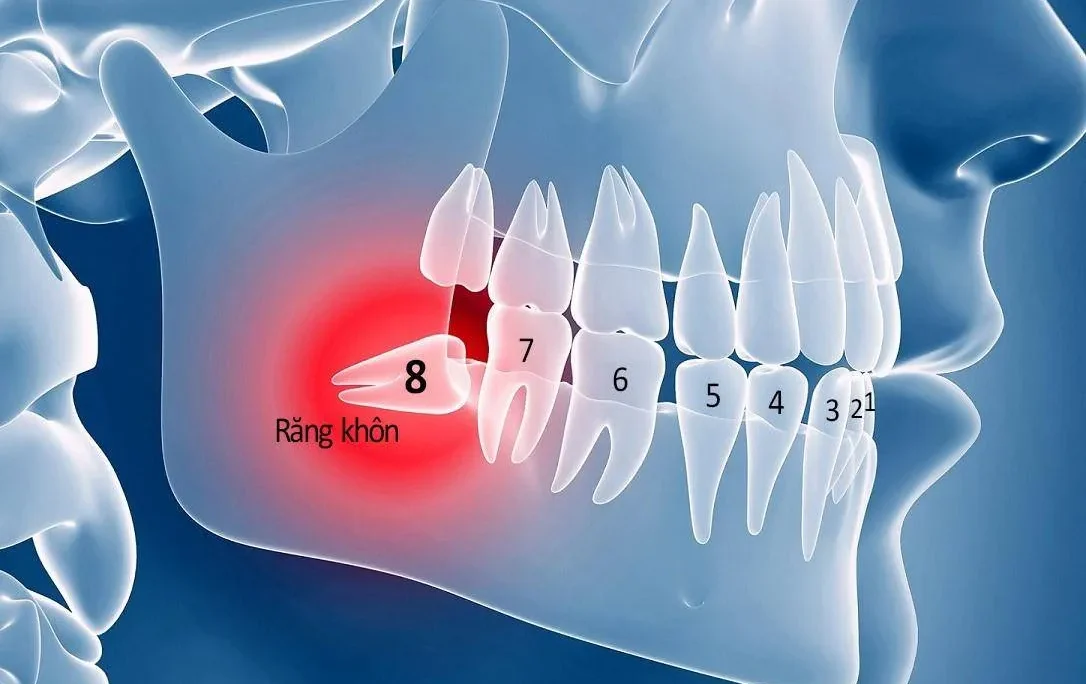

Răng số 8 hay răng khôn là một trong những chiếc răng phiền toái nhất với bất kì ai. Loại răng này khi mọc thường khiến bạn cảm thấy đau đớn, khó chịu và ảnh hưởng đến sinh hoạt. Chính vì thế mà việc nhổ chiếc răng này là điều mà bạn nên thực hiện. Tuy nhiên, để có thể nhổ răng số 8 an toàn thì cần đến nha khoa uy tín. Với tư cách là nha khoa uy tín nhất Quảng Ninh, Nha khoa DrGreen xin cung cấp dịch vụ nhổ răng số 8 tại Quảng Ninh an toàn hiệu quả và không đau tới các bạn. Hãy cùng tìm hiểu trong bài viết này

Nhổ răng số 8, còn được gọi là nhổ răng khôn, là một thủ thuật nha khoa nhằm loại bỏ một hoặc nhiều chiếc răng hàm thứ ba. Đây là các răng vĩnh viễn mọc ở vị trí cuối cùng của hàm trên và hàm dưới. Lúc này những răng khôn không có đủ không gian để mọc hoàn chỉnh. Vì thế chúng có thể gây ra đau đớn, viêm nhiễm bề mặt lợi và răng. Thậm chí dẫn đến những vấn đề nghiêm trọng về sức khỏe răng miệng. Trong trường hợp này, việc nhổ bỏ răng khôn là cần thiết để ngăn ngừa các biến chứng.

Răng số 8 thường bắt đầu mọc trong giai đoạn từ 17 đến 25 tuổi. Tuy nhiên, sự hiện diện và số lượng răng khôn ở mỗi người có sự khác biệt đáng kể. Một số người có đầy đủ bốn chiếc răng khôn. Chúng phân bố ở bốn góc hàm bao gồm trên trái, trên phải, dưới trái, và dưới phải. Ngược lại, có những trường hợp chỉ có 1, 2 hoặc 3 chiếc răng khôn. Hoặc thậm chí không có răng khôn nào.

- Răng mọc lệch, mọc ngầm hoặc mọc ngang dẫn đến tình trạng chen chúc. Từ đó làm xô lệch toàn bộ hàm răng, gây mất cân đối khớp cắn và ảnh hưởng thẩm mỹ.

- Răng số 8 mọc chèn ép vào dây thần kinh dưới nướu. Theo thời gian chúng = có thể gây tổn thương nghiêm trọng. Tình trạng này dẫn đến giảm hoặc mất cảm giác ở vùng niêm mạc miệng, môi, da. Thậm chí có thể ảnh hưởng đến vùng thái dương hoặc gây đau đầu kéo dài.